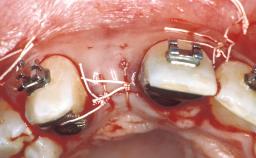

| Case Type | Extended Space |

| Jaw | Maxilla |

| Area | Anterior |

| # of Teeth | 4 |